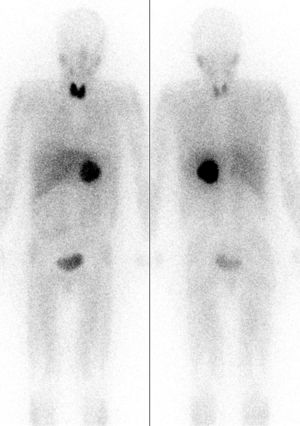

يمكن أن يساعد التصوير المقطعي المُحَوْسب أو التصوير بالرنين المغناطيسي T2 على الرأس والرقبة، والصدر، والبطن في تحديد مكان الورم. ويمكن أيضًا تحديد المكان عن طريق المسح الضوئي MIBG، باستخدام metaiodobenzylguanidine . أما التحديد الأدق فيمكن الحصول عليه في بعض مراكز المسح باستخدام PET-CT أو PET-MRI مع 18F] fluorodopamine] أو FDOPA.[10]

ورم القواتم الثنائي في MEN 2.